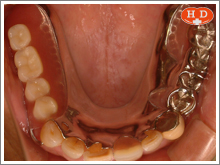

上下の残存歯の位置がすれ違っていて、通常の入れ歯では良好な機能を維持するのが難しい状態です。

コーヌステレスコープ義歯を用いることによって、咬む力を土台の歯全体で受け止め、完成後6年を経ていますが安定しています。

(症例写真は院長の母親です。)